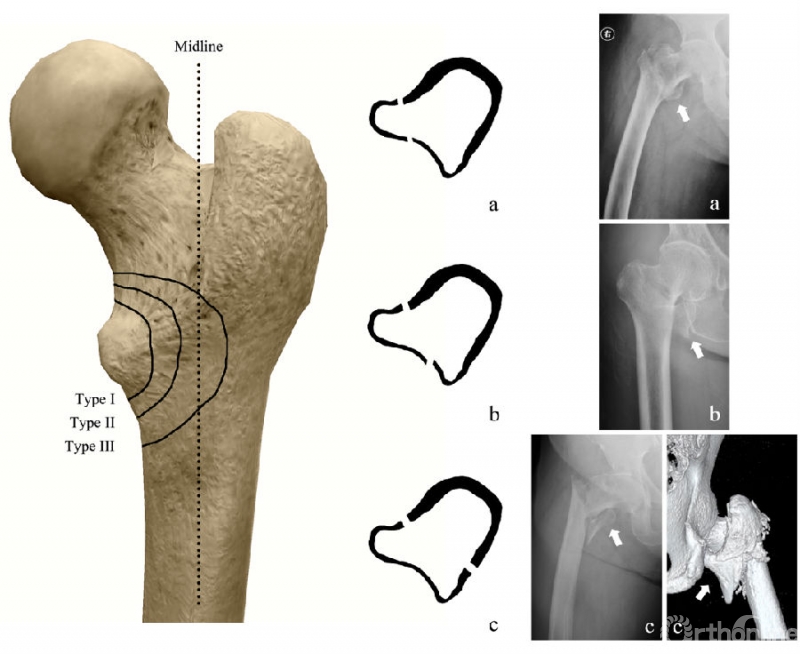

2. 内侧壁骨折分型:通过术前影像学资料,将内侧壁骨折分为3型(图2):

(1)Ⅰ型:小粗隆撕脱,骨折线没有越过小粗隆基底部;

(2)Ⅱ型:整块或粉碎的骨折块,包含小粗隆附近的后侧壁皮质,骨折线没有达到后侧壁中线;

(3)Ⅲ型:整块或粉碎的骨折块,骨折块包含大量后侧壁皮质,骨折线达到或超越后侧壁中线。

分型由2位有经验的骨科医师共同评定得出,Ⅰ型和大部分Ⅱ型骨折可以通过X线确定,少部分Ⅱ及所有Ⅲ型骨折须通过CT及3D重建确定。

图2: 内侧壁骨折的分型示意图

考虑到既往的生物力学研究显示,越大的内侧壁骨折块对股骨粗隆间骨折模型的力学性能影响越大,为了进一步研究内侧壁骨折对髓内钉术后稳定性的影响,我们提出了一种针对内侧壁骨折的分型(详见图2)。

考虑到合并Ⅲ型内侧壁骨折的粗隆间骨折内固定失败率显著升高,我们认为术前应识别AO/OTA A2型骨折中的Ⅲ型内侧壁骨折块,如有必要,强烈建议完善CT扫描和3D图像。经过对62例合并Ⅲ型内侧壁骨折的股骨粗隆间骨折病例术前影像学资料的回顾,我们发现,Ⅲ型内侧壁骨折在形态学上可以分为三大类(图5):“含小粗隆型(fragment with lesser trochanter, LT)” (占比67.7%)、 “含大小粗隆型(fragment with greater and lesser trochanter, GLT)” (占比24.2%) 和“ 粉碎型(comminuted fragments)”(占比8.1%)。

图5:Ⅲ型内侧壁骨折的三种形态:(a)含小粗隆型(LT);(b)含大小粗隆型(GLT);(c)粉碎型(comminuted)